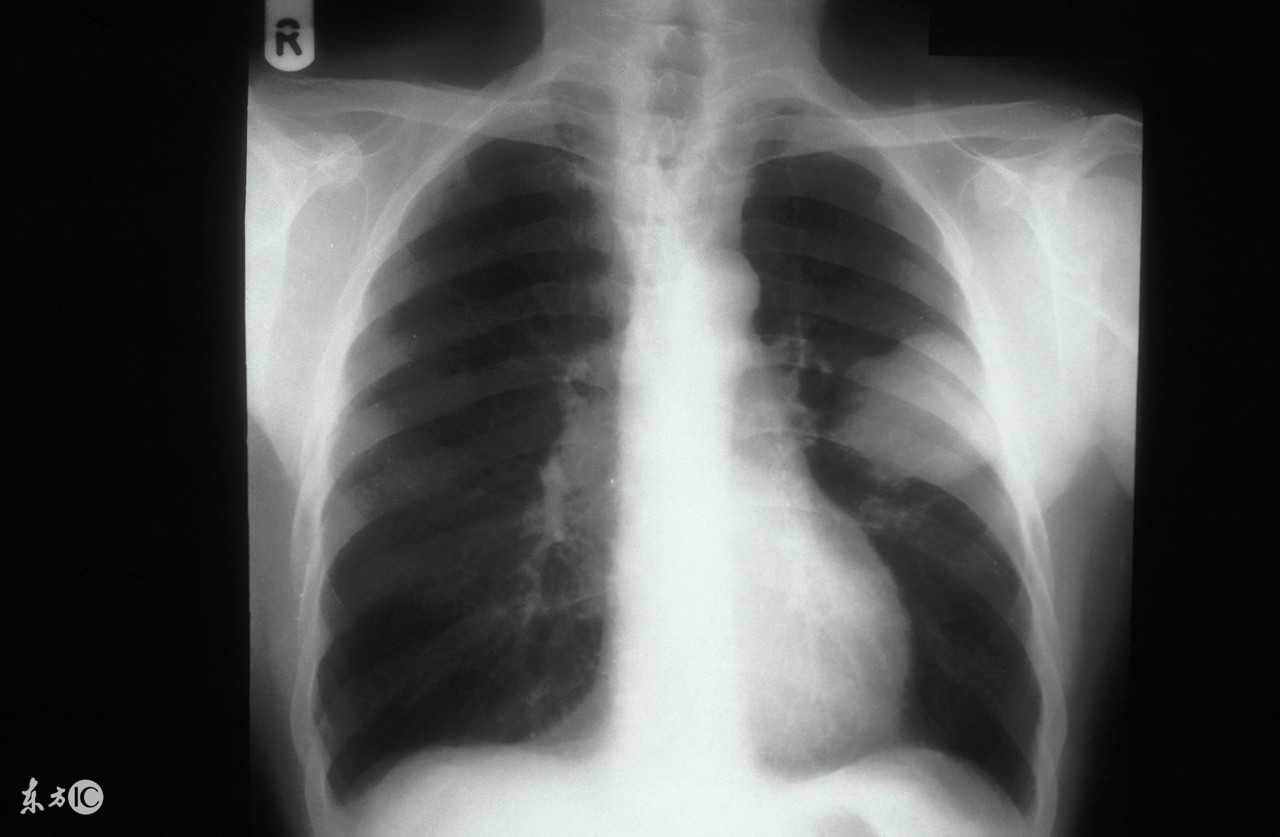

近些年来肺癌的发病率是越来越高了,成为威胁人类健康的重要“杀手”之一,一说到肺癌大家就会想到死亡,但是近些年来随着医学技术水平的不断提高,肺癌的治疗得到了很大的提高,因此大家也不必太担心了。大多数已发生胸内区域性播散的肺癌患者均有胸痛之症状,其次是声嘶。最后还会导致面、颈部水肿。最终,发生区域性扩散的肺癌患者几乎都有不同程度的气促。那么肺癌治疗不及时会导致哪些并发症呢?下面我们一起来了解一下吧。